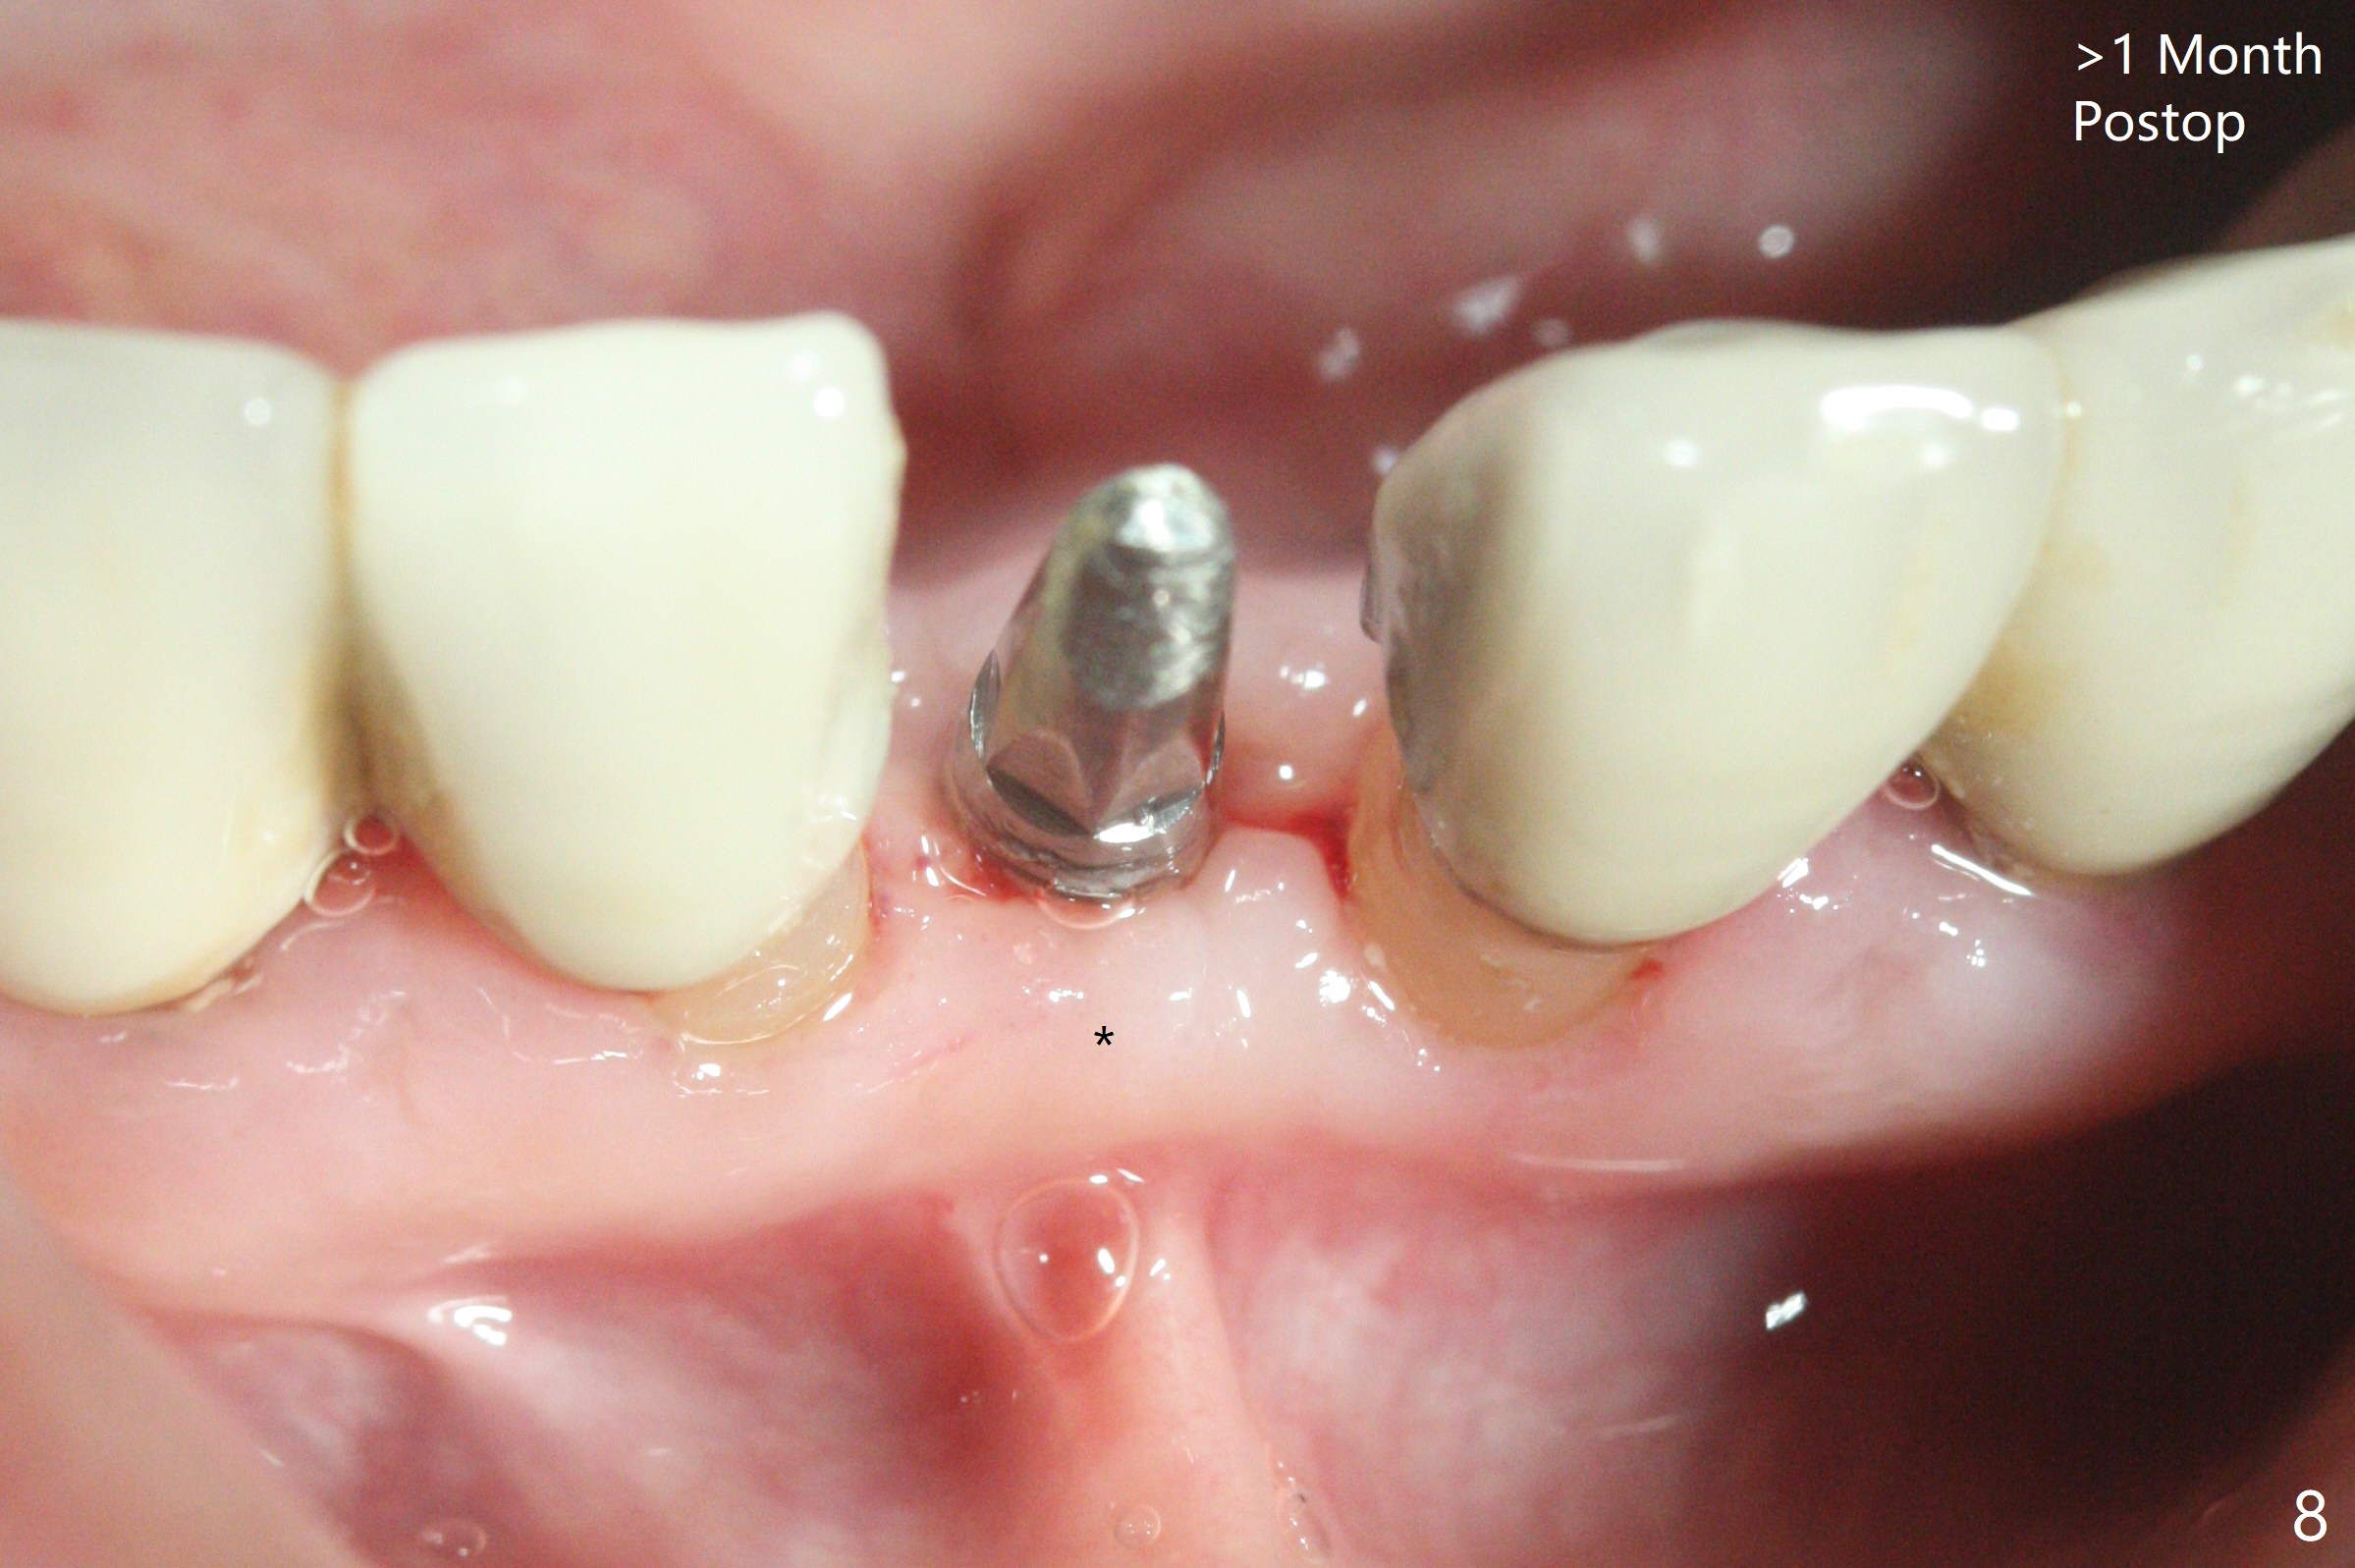

种植前与66岁女病人再次讨论下前牙正中种植可能产生不对称问题,她好像不在乎。术前检查显示下前牙正中间隙偏左(图一),处理似乎容易,但是牙槽嵴相当狭窄(图一 *,二 箭头)。牙槽嵴切除后(大约3 毫米宽(颊舌侧)),初期钻洞似乎偏移右边(图三),矫正后(图四),植入2乘10(4)毫米连体植体(图五,比预计小,因为骨质薄),放置骨粉(图五,六 *)和膜,缝合,制作即刻修复物(图七 T),病人满意,牙槽骨饱满了。术后一个多月临时牙冠取出修正,伤口愈合,由于植骨颊侧没有凹陷(图八),而舌侧隆起(图九:*,与图二术前对比)。其实病人不小心吃牛肉时损伤植体,疼痛几天。尽管最近吃饭时植牙又受伤,但是没有松动,也没有骨质吸收,就是局部结石多(图十,术后四个月)。正式牙冠术后4.5个月粘固(图十一)。